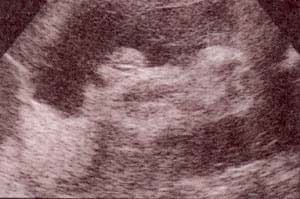

fig. 50. – (c). 30 semanas. los testículos dentro del escroto. fig. 50. – (d). 36 semanas. corte sagital. se observa el canal uretral.